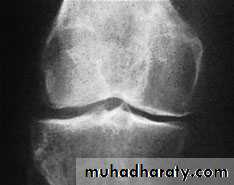

X-ray

The anteroposterior x-ray must be obtained with the patient standing and bearing weight; only in this way can small degrees of articular cartilage thinning be revealed.1-The tibio-femoral joint space is diminished

(often only in one compartment) and there is

2-subchondral sclerosis.

3-Osteophytes and

4- subchondral cysts

5-chondrocalcinosis are usually present and sometimes there is soft-tissue calcification in the suprapatellar region or in the joint

itself

X-ray Non weight bearing